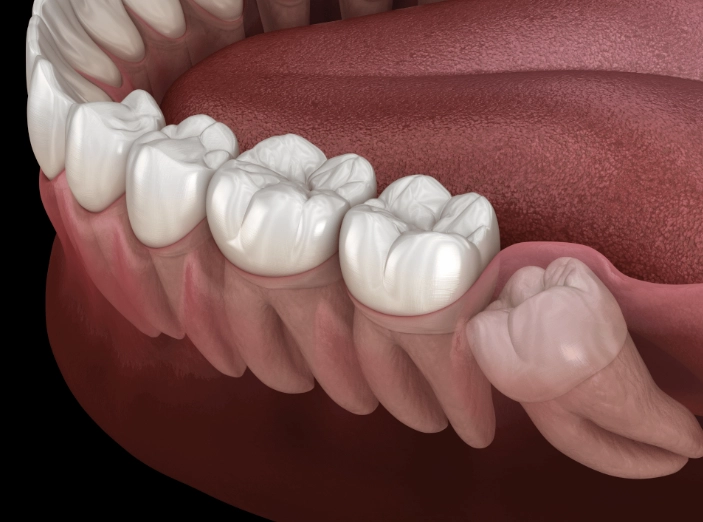

Pericoronitis: The Infection You Can Feel

This is a big one. When a wisdom tooth partially erupts, a flap of gum tissue often remains over it. This flap is a perfect trap for food particles and bacteria. The resulting infection—pericoronitis—causes intense, localized pain, swelling, a bad taste, and sometimes difficulty opening your mouth. It's a clear signal that the area is no longer manageable with brushing alone.

Crowding and Decay

Even if a wisdom tooth manages to come in fully, it's often so far back and angled so awkwardly that it's impossible to clean properly. Plaque builds up rapidly, leading to cavities in the wisdom tooth itself and the precious molar in front of it. The pain from this decay can be sharp and sensitive to temperature or sweets.